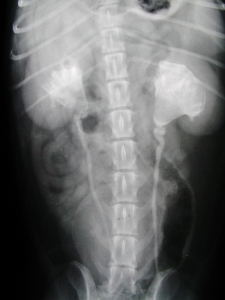

下の二枚の写真は6歳のウエル・シュコーギーでみられた両側性の巨大な腎結石のレントゲン写真です。「おにぎりのような三角形」のような2つの大きな塊が腎結石で、腎結石は腎盂(つくられた尿が溜まる場所)をほぼ占拠して腎臓を内側から強く圧迫していました。

写真は静脈性尿路造影のもので、腎臓から膀胱に白い筋状にみえる尿管と白い卵型に見える膀胱も一緒に造影されて写っています。この腎結石は将来的な腎機能不全のリスクが高いため、両側とも手術により摘出いたしました。ここまで結石が大きく育つのは稀なことですので、腎結石の極端な例としてご覧ください。